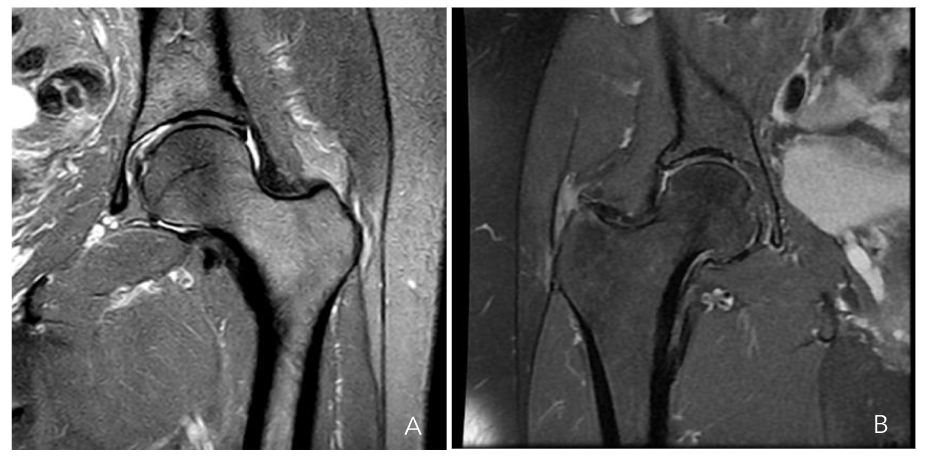

Figure 6a-b. Hip MRI scan showing a partial gluteus medius tear (a) and a gluteus minor tear (b)

The selection of an appropriate treatment modality becomes more complex when lesions affect between 25% and 50% of the thickness Figure 7. As previously noted, these lesions are situated medial to the gluteus medius tendon, demonstrating tendon continuity in the most lateral region. Direct repair of this lesion would require the disinsertion of a healthy gluteus medius tendon, which is suboptimal. Cutting one healthy tendon to repair another would, at best, result in scar tissue formation, which would not possess the same functionality as native tissue. Consequently, in this subset of lesions, augmentation with a biological collagen patch is employed, in addition to the technique described for the two previous groups.

Figure 7. Hip MRI scan showing a 30% rupture of the gluteus medius and minor tendons